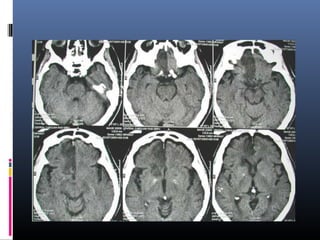

Conventional MRI in acute

stroke- T2 and FLAIR

• These sequences detect 80%

infarct before 24 hrs

• It can be negative upto 2 to 4

hrs

Temporal sensitivity

Spacial sensitivity

After 55 min

After 5 hrs

Conventional MR imaging

Hyperacute infarct Subacute infarct